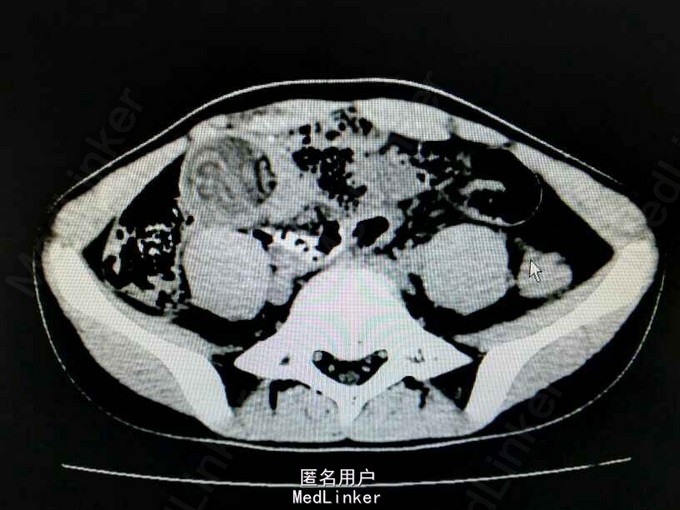

患儿,男,13岁,因“黑便伴右下腹痛7 小时”入院。 患者7小时前无明显诱因出现腹痛,位于右下腹,为持续性绞痛,休息可缓解,疼痛无放射 至其它部位,伴有恶心、呕吐,无伴发热、返酸、嫒气、腹胀、腹泻、呕血、黑便、血便, 遂到我院急诊就诊,行腹部CT 提示”考虑肠套叠,局部肠管水肿”,为进一步诊治,急诊 拟“腹痛查因:肠套叠”收入我科。

腹平,腹软,脐周及右下腹压痛,反跳痛可疑,腹部移动性浊音(-),肠鸣音4次份。 腹部ct提示“下腹部局部小肠肠壁明显增厚,密度减低,局部可见肠管套入,可见多层肠壁显示。考虑肠套叠,局部肠管水肿”。